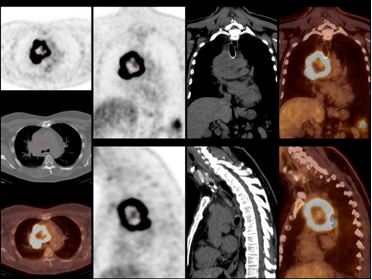

Ghi hình phát hiện các khối u trong phổi, YHHN đã và đang phát triển mạnh. Hiện nay SPECT, SPECT/CT, PET và PET/CT đã cho những hình ảnh định lượng về giải phẫu và chức năng cụ thể, nâng cao hiệu quả chẩn đoán và điều trị. Dưới đây ví dụ vài hình ảnh cụ thể:

PET/CT ghi hình u phổi

Đặc biệt hiện nay, PET/CT trên thế giới và ở Việt Nam đang phát triển và ứng dụng nhiều và có hiệu quả cao trong chẩn đoán, theo dõi đáp ứng điều trị và tiên lượng trong các bệnh về phổi .